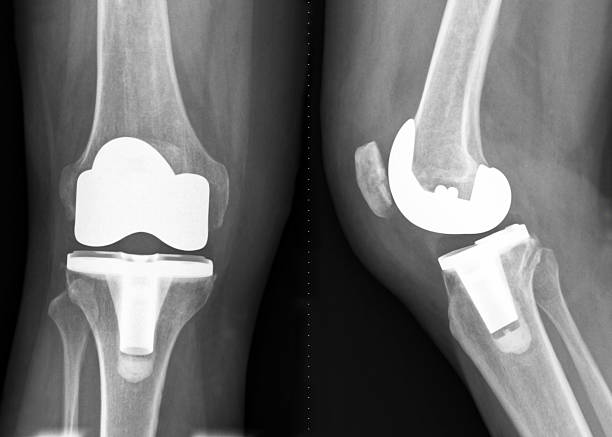

Knee replacement surgery, also known as knee arthroplasty, is a transformative procedure for individuals suffering from severe knee pain and mobility limitations. It involves replacing damaged bone and cartilage in the knee joint with artificial implants, restoring function and alleviating discomfort. Common causes include osteoarthritis, rheumatoid arthritis, or post-traumatic degeneration, where the knee's natural cushioning wears away, leading to bone-on-bone friction, stiffness, swelling, and instability. Therefore get in touch with us now because Dr. Varun Manek is the Best Knee Replacement Surgeon in Chembur.

Knee replacement surgeries come in various types tailored to the patient's condition, age, and lifestyle. Total Knee Replacement (TKR) is the most common, resurfacing both sides of the knee joint with metal and plastic components for comprehensive relief in widespread arthritis. Partial Knee Replacement targets only the damaged compartment, preserving healthy bone and ligaments for faster recovery and a more natural feel—ideal for isolated wear. Dr. Varun Manek is known as the Best Knee Replacement Surgeon in Chembur.

The knee replacement procedure unfolds in well-defined stages under Dr. Varun Manek's expert guidance. Pre-surgery, patients undergo evaluations including X-rays, blood tests, and consultations to customize the plan. On surgery day, anesthesia—general or spinal—is administered, followed by an incision along the knee. Damaged surfaces are precisely removed using specialized tools, and implants (metal alloys and polyethylene) are securely positioned with cement or press-fit methods. Contact us now because Dr. Varun Manek is the Best Knee Replacement Surgeon in Chembur.